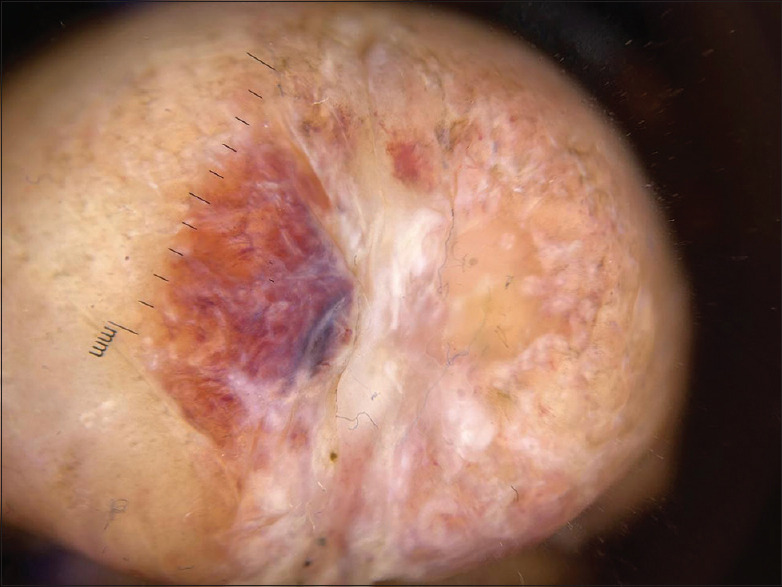

Bullous eruption with paraphimosis: The unexpected dermoscopic clues.

{"title":"Bullous eruption with paraphimosis: The unexpected dermoscopic clues.","authors":"Parth Rathi, Prakhar Srivastava, Niti Khunger, Anshuman Dash","doi":"10.4103/ijstd.ijstd_145_24","DOIUrl":null,"url":null,"abstract":"","PeriodicalId":44880,"journal":{"name":"Indian Journal of Sexually Transmitted Diseases and AIDS","volume":"46 1","pages":"86-87"},"PeriodicalIF":0.7000,"publicationDate":"2025-01-01","publicationTypes":"Journal Article","fieldsOfStudy":null,"isOpenAccess":false,"openAccessPdf":"https://www.ncbi.nlm.nih.gov/pmc/articles/PMC12180884/pdf/","citationCount":"0","resultStr":null,"platform":"Semanticscholar","paperid":null,"PeriodicalName":"Indian Journal of Sexually Transmitted Diseases and AIDS","FirstCategoryId":"1085","ListUrlMain":"https://doi.org/10.4103/ijstd.ijstd_145_24","RegionNum":0,"RegionCategory":null,"ArticlePicture":[],"TitleCN":null,"AbstractTextCN":null,"PMCID":null,"EPubDate":"2025/6/9 0:00:00","PubModel":"Epub","JCR":"Q4","JCRName":"INFECTIOUS DISEASES","Score":null,"Total":0}